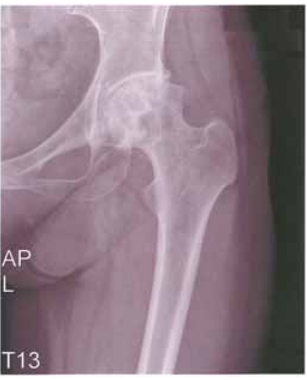

26 44 歲官小姐,罹患左髖關節疼痛已經 3 年,其 X 光檢查如圖所示。此病可能與下列何種藥物長期服 用有關?

(A) NSAID 止痛藥 (B)古柯鹼 (C)類固醇 (D)支氣管鬆弛劑